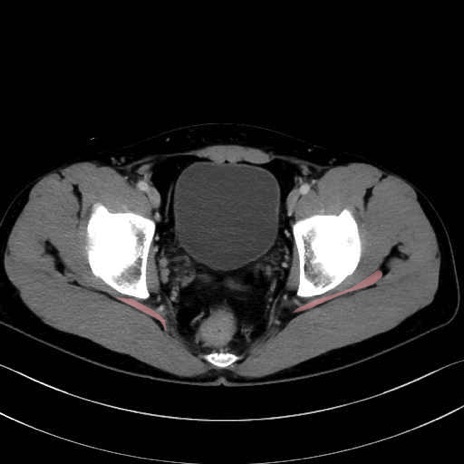

梨状筋 (Piriformis)